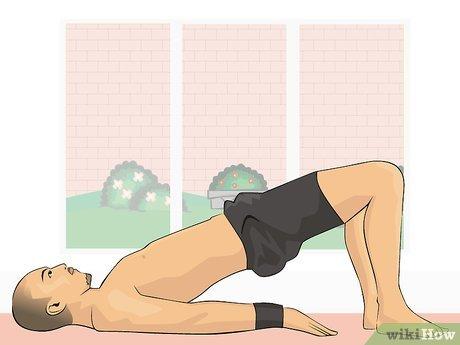

Гимнастика Кегеля для мужчин: упражнения для простаты